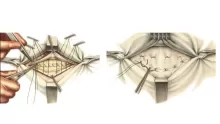

- لا يمكن تحديد نوع الجنين بشكل قطعي إلا من خلال بواسطة جهاز السونار، الذي يعمل بالموجات الفوق صوتية. يمكن للحامل إجراء هذا الفحص من أول شهر 4 للرؤية العضو التناسلي للجنين، وبالتالي معرفة جنسه. يعد السونار أدق شيء يمكن التعرف على نوع الجنين من خلاله.